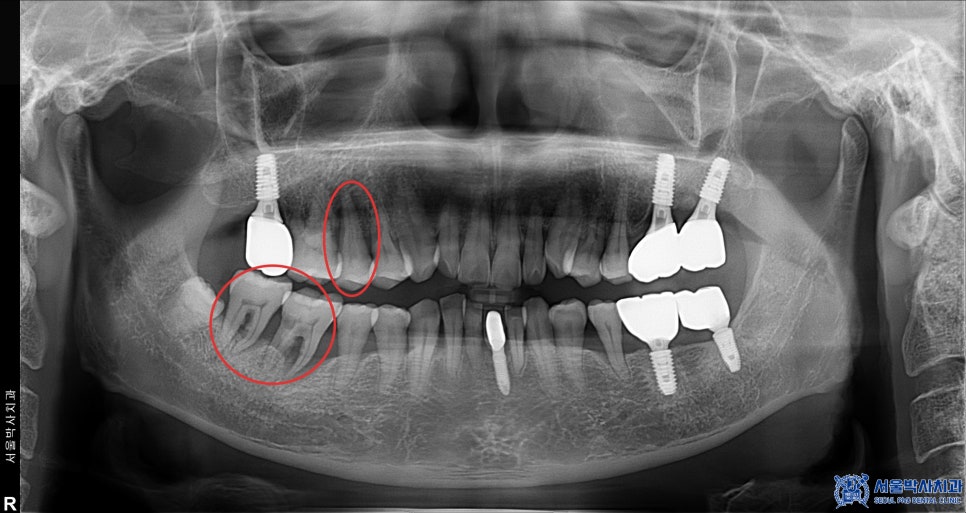

위 환자분은 50대 중반의 남성분으로,

오른쪽 위, 아래 어금니 잇몸이 많이 붓고

흔들림과 통증이 있다고 하셨습니다.

진단 결과, 상악 우측 작은 어금니와

하악 우측 큰 어금니 2개 부위에

만성복합염증이 광범위하게 퍼져 있었고,

염증으로 인해 뼈도 많이

손실된 상태였습니다.

이로 인해 세 치아 모두 흔들림이 심했고,

보존하기 어려운 상태였기에

발치 후 임플란트를 결정하였습니다.